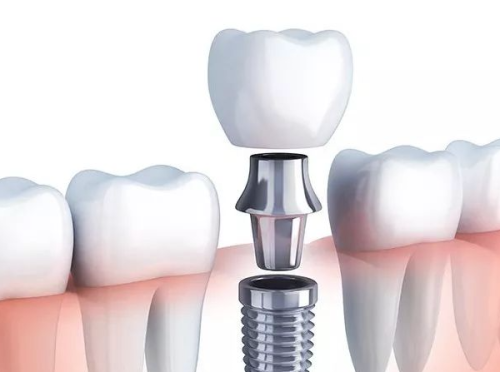

要弄清楚种植牙多少钱一颗,就得先了解其费用的构成。种植牙的费用包含多个部分,首先是种植体的费用,种植体就相当于牙齿的“根”,它的材质、品牌不同,价格也会有较大差异。其次是手术费,这是医生为患者进行种植牙手术所收取的费用,手术的复杂程度会影响手术费的高低。还有麻醉费,在种植牙手术过程中,为了减轻患者的痛苦,需要进行麻醉,麻醉的方式和药物也会产生一定费用。另外,检查费也必不可少,在进行种植牙手术前,需要对患者的口腔进行全方面检查,包括X光片、CT等,以确定患者的口腔状况是否适合种植牙。末尾是术后护理费,术后需要对种植牙进行护理和维护,这也会产生一定的费用。